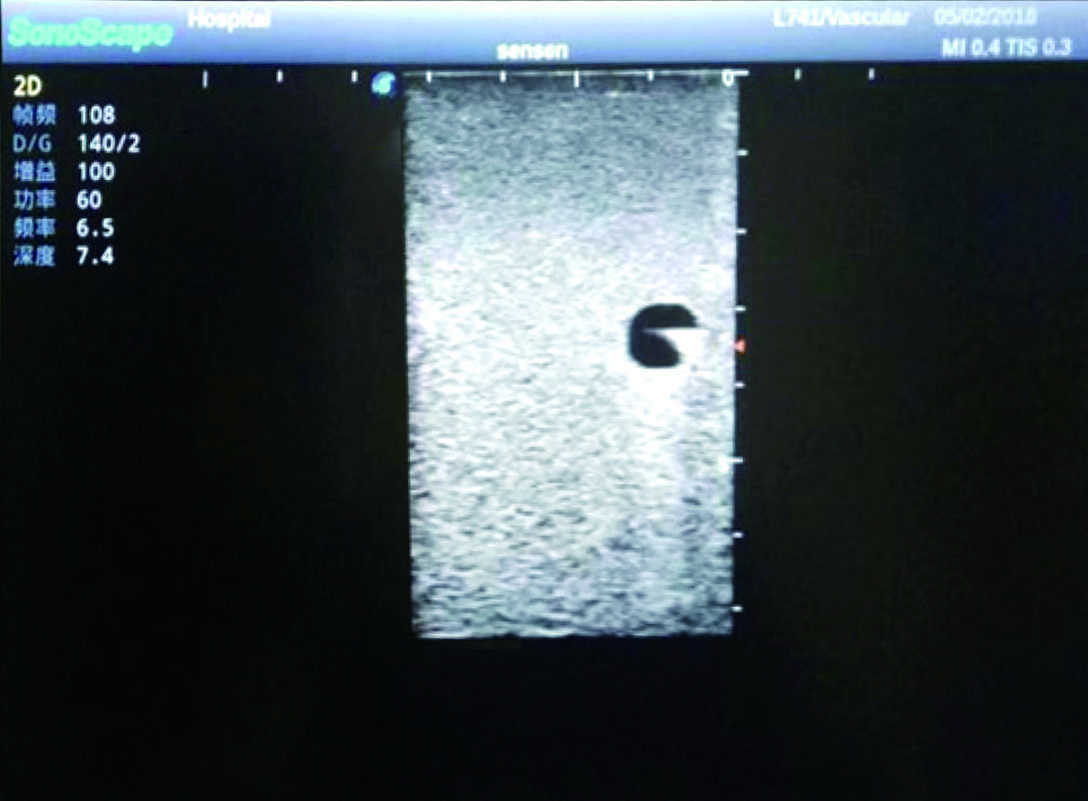

2) It can be used by real ultrasound machines

3) Clear and real images of the tissues and organs (basilic vein and superior vena cava)

4) When conducting vascular puncture, the piercing can be truly felt, and venous blood outflow can be seen